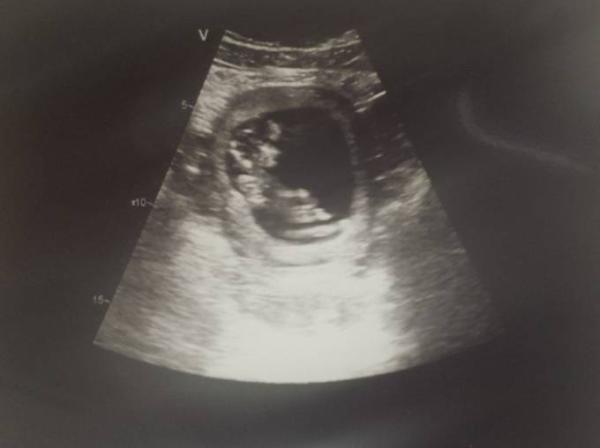

Hab heute in der Arbeit (bin Krankenschwester) nen Ultraschall gemacht und musste jetzt einfach meine Freude mit euch teilen War so süß wie das kleine rumgeturnt ist und hab echt ein wunderschönes Bild gemacht

Bild zu Ultraschall - Forum für Juli - Mamis

Wow sehr schön ist das Bild Ich habe auch so ein ähnliches aus der 13ten Woche, nur das mein kleines Kopfstand macht